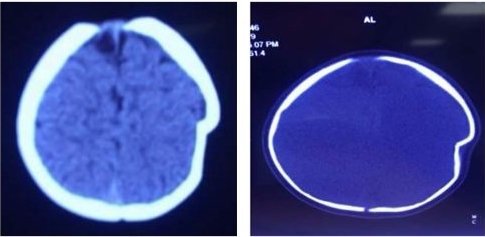

Kết quả kiểm tra cận lâm sàng, bệnh nhi được chẩn đoán lún sọ thái dương đỉnh trái 1cm. Để điều trị, bệnh nhi được chỉ định phẫu thuật.

Hình ảnh phim chụp sọ não bệnh nhi trước và sau khi phẫu thuật.

"Sau khoảng 8 ngày điều trị, bệnh nhi ổn định trở lại, sức khỏe, thể trạng phục hồi tốt và vừa được ra viện", bác sĩ Tài nói.